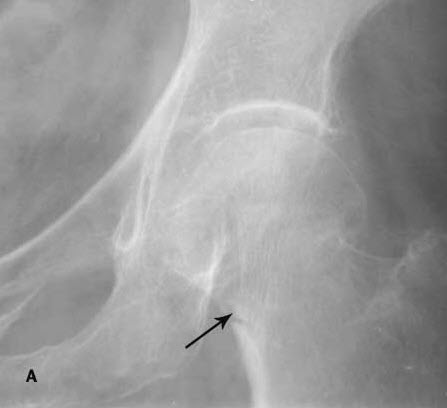

For years, physicians have advised postmenopausal women to take calcium and vitamin D supplements to reduce their risk of osteoporosis and the debilitating fractures associated with that disease (Figure). To test the premise for this widely recommended intervention, investigators from the WHI randomly assigned more than 35,000 postmenopausal women, aged 50 to 79 years, who were already enrolled in a WHI clinical trial, to receive either 1000 mg of elemental calcium (as calcium carbonate) with 400 IU of vitamin D3 daily--or placebo. They monitored the women, measuring their bone density and tracking fractures, for an average of 7 years.1